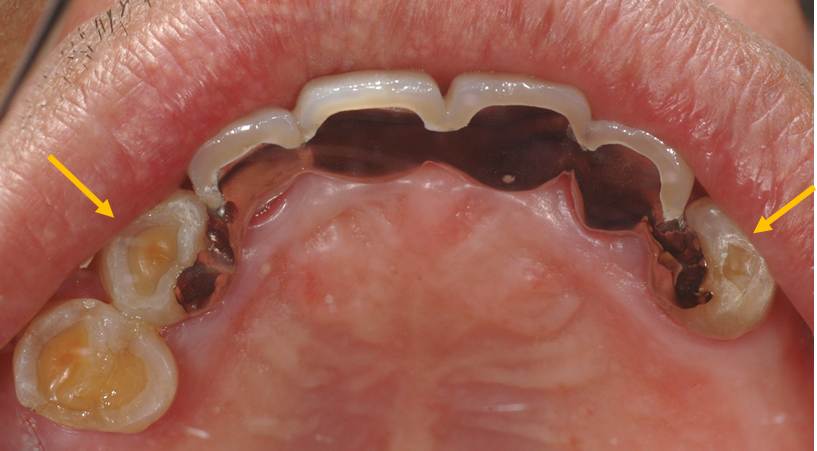

まずエックス線所見です。○で囲んだ部分に骨吸収が認められます。